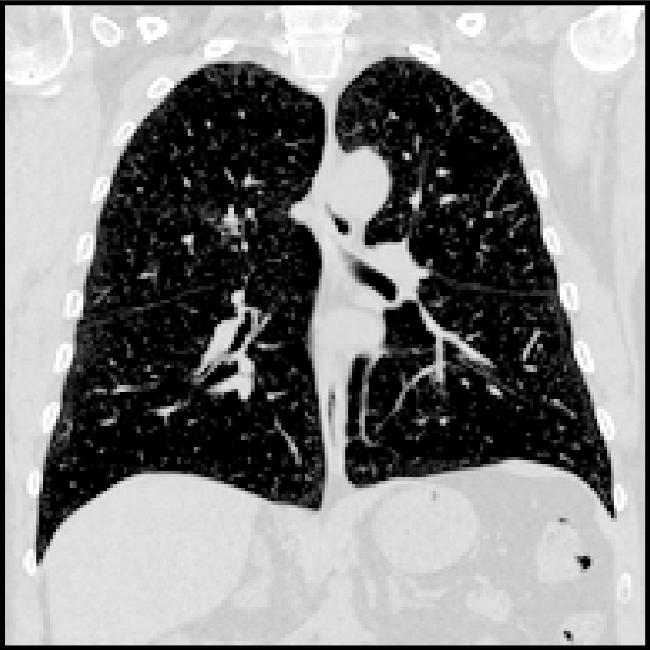

Lung CT

The aim of the lung CT task was the registration of expiration to inspiration CT scans of the lung. Establishing correspondences between longitudinal lung scans can help to monitor disease progression, estimate motion in radiotherapy planning or enable direct assessment of lung ventilation. The data consists of 20 training [33] and 10 test scan pairs [34]. The scans were acquired at the Dept. of Radiology at the Radboud University Medical Center, Nijmegen, NL. All pairs were affinely pre-registered and resampled to an image size of 192×192×208192192208192{\times}192{\times}208. Lung segmentation masks and keypoints were provided as additional training information. The complexity of this registration task is manifold. First, the fields of view of the fixed and moving scan differ largely since the lungs in the expiration scan are not fully visible. Second, the scale of the motion within the lungs can often be larger than the anatomical structures (vessels and airways) themselves. Therefore, a registration method needs to estimate large displacements that account for substantial breathing motion and also align small structures like individual pulmonary blood vessels precisely. To measure the accuracy manual landmarks are used that are typically located at the boundary or bifurcation of vessels, airways, and parenchyma.